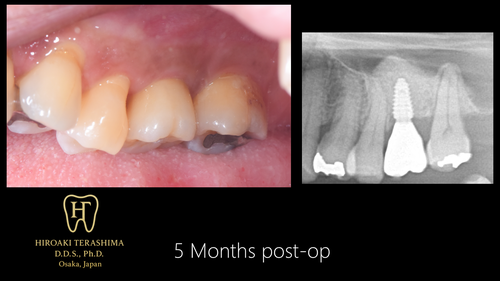

【経過】

X線でもインプラント周囲骨の成熟化が確認できました。